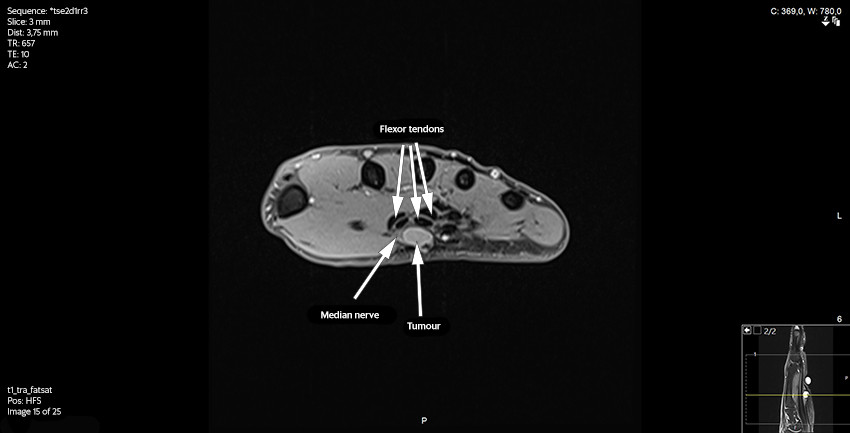

The patient was then referred for an MRI scan at a private clinic and subsequently to the orthopaedic department at the regional hospital. Following the MRI scan, the radiologist reported a contrast-enhancing, well-defined soft tissue tumour adjacent to or on the median nerve at the outlet of the carpal tunnel. It was concluded that the tumour was consistent with a schwannoma, but that another type of tumour could not be ruled out (Figures 2 and 3).

The patient was immediately informed about the biopsy result and referred to a sarcoma centre. The preoperative images from the MRI scan were re-assessed by radiation oncologists. They concluded that there was a solid vascularised tumour along the median nerve with no typical 'target sign' or 'fascicular sign' as often seen in benign nerve sheath tumours. It was not possible to make a more precise diagnosis on the basis of the preoperative MRI images. Chest CT, abdominal CT and ultrasound of axillary nodes revealed no signs of metastases. A repeat MRI scan of the hand showed no residual tumour. Due to the tumour's location adjacent to a major nerve and tendons, an expanded resection was not advised. The patient received postoperative radiotherapy, 2 Gy × 30, to reduce the risk of local recurrence. At the next follow-up, the wounds had healed following the radiotherapy. The patient had no nerve pain or neurological deficit.